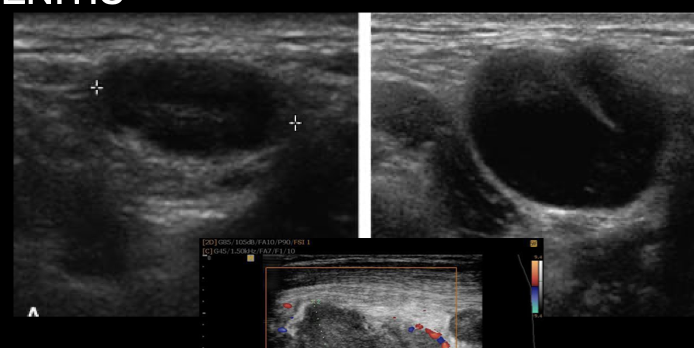

Linfadenitis